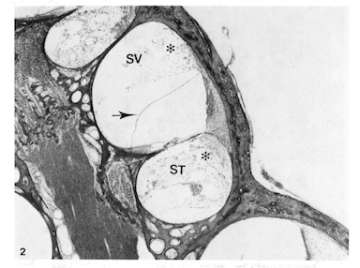

(A) Middle turn of cochlea of the chinchilla 12 hours following endotoxin instillation. Inflammatory cell infiltration and bleeding (*) are seen in perilymphatic spaces and spiral ligament with mild endolymphatic hydrops (arrow). SV: scala vestibuli, ST: scala tympani.